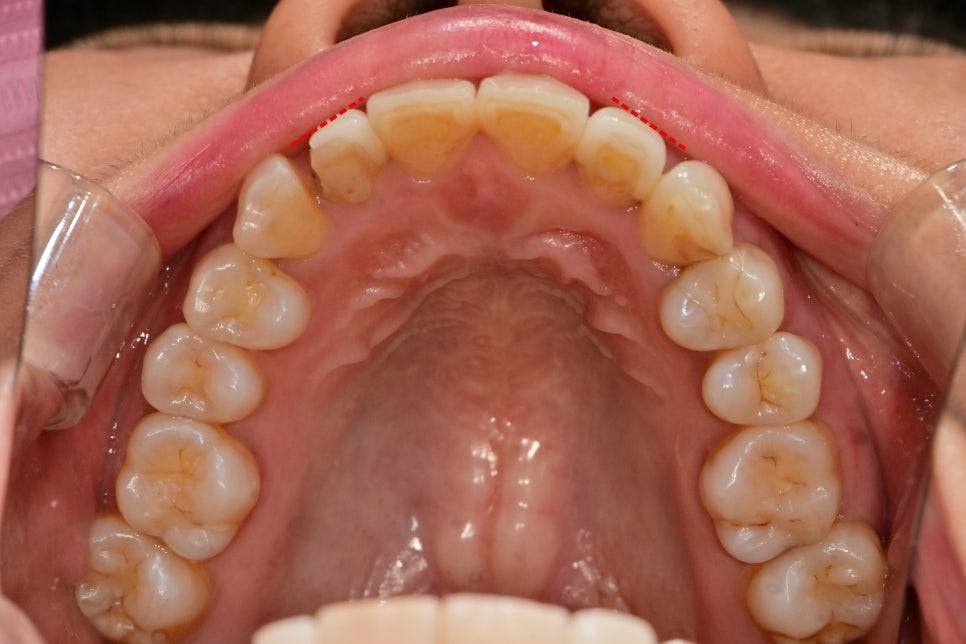

기존라미네이트를 위에서 바라본 사진입니다.

치아의 돌출정도가 다르지만 일률적으로

치아를 다듬고 같은 두께로 제작하다 보니

한쪽의 치아가 더 돌출되어 보이고 이는 입체적으로

부조화를 야기할 수 있습니다.

이런 것을 해소하기 위해 진단모형으로

치아 삭제량을 결정할 수 있습니다.